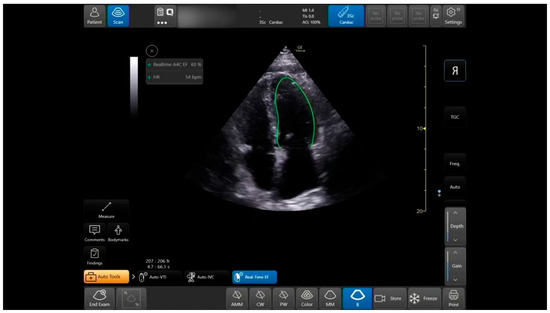

VTI Automatic Measuring Tool

The auto VTI tool is based on proprietary artificial intelligence. The tool automatically places the cursor on the left ventricular outflow tract (LVOT) and auto-traces the velocity waveforms to calculate the VTI. The tool then calculates VTI and CO by averaging all Doppler waveforms during a period of four seconds. Calculations were performed in real-time, and the results are displayed in the Results Box (Figure 5). The Quality Indicator is represented by the color of the curser placed by the system over the LVOT. It varies between green/yellow/red to represent excellent/average/unacceptable image quality, respectively.

7.3. LVOT VTI

One hundred and fourteen apical five-chamber view clips were acquired from 32 patients. The clips were taken in pairs—a POCUS expert acquired a clip, and then without changing the probe position acquired a second, similar clip. Thus, two groups of paired clips were formed. Patients were primarily males (69%), with a mean age of 57.4 ± 18.5 and a mean body mass index (BMI) of 27.1 ± 5.5 (Table 1). When assessed by the Expert, the mean LVOT VTI value was 19.5 ± 4.5 and 17.7 ± 4.3 by the automatic analysis read. The Intraclass Correlation Coefficient for agreement between the automatic and physician-assessed quantifications was 0.825 (95% CI 0.659, 0.905; p < 0.001). In the high clips’ quality subgroup, the Intraclass Correlation was reduced to 0.655 (95% CI 0.013, 0.877; p = 0.024). In the medium clip quality group, the Intraclass Correlation was 0.914 (95% CI −0.077, 0988; p < 0.001) (Table 4). For the image quality agreement, we found a significant difference (p = 0.167, Fishers Exact test value—3.26, α) in the agreement of quality between the physicians’ group and the automatic tools group.

The VTI agreement proved to be very high in all levels of the acquired image quality; high, medium, and total. This finding confirms that when a quick measurement for stroke volume is needed, there is a reliable automatic tool for any level of imaging quality.

Figure 5. Auto VTI tool. When in Apical5Chamber-View. Auto marker placement, velocity pattern measurements and data display.